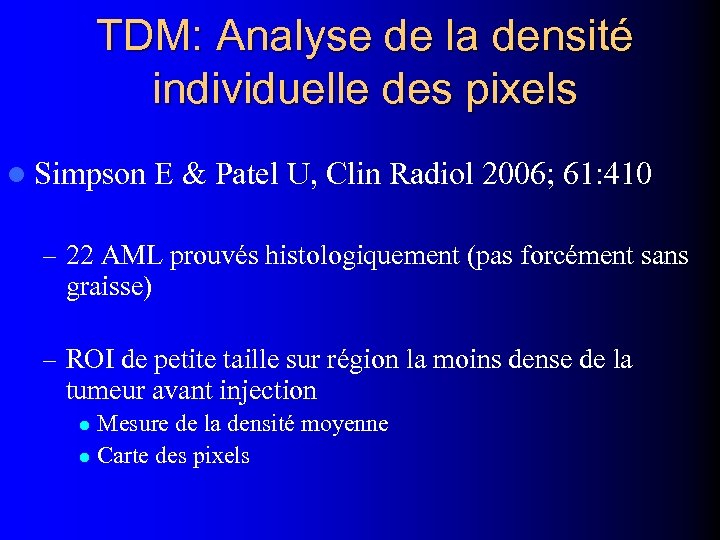

TDM: Analyse de la densité individuelle des pixels l Simpson E & Patel U, Clin Radiol 2006; 61: 410 – 22 AML prouvés histologiquement (pas forcément sans graisse) – ROI de petite taille sur région la moins dense de la tumeur avant injection Mesure de la densité moyenne l Carte des pixels l

TDM: Analyse de la densité individuelle des pixels l Simpson E & Patel U, Clin Radiol 2006; 61: 410 – 22 AML prouvés histologiquement (pas forcément sans graisse) – ROI de petite taille sur région la moins dense de la tumeur avant injection Mesure de la densité moyenne l Carte des pixels l

l Ligne ou carré d'au moins 4 pixels contigus dont la densité est ≤ -10 UH: – Se: 86% ; Spe: 97% l ROI avec densité moyenne ≤ -10 UH: – Se: 73% ; Spe: 100%

l Ligne ou carré d'au moins 4 pixels contigus dont la densité est ≤ -10 UH: – Se: 86% ; Spe: 97% l ROI avec densité moyenne ≤ -10 UH: – Se: 73% ; Spe: 100%